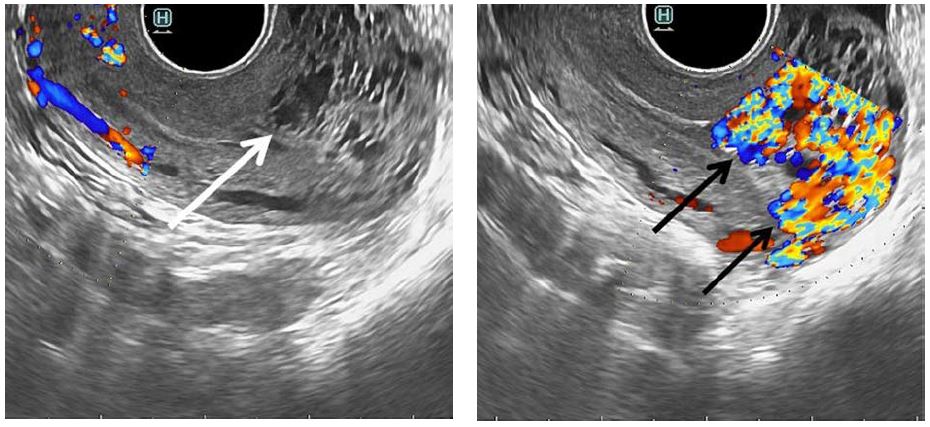

During admission, she was found hemodynamically stable, but moderate vaginal bleeding was observed. Laboratory results were as follows: haemoglobin – 9.5 g/dL, haematocrit – 33.5%, beta-human chorionic gonadotropin – 16.6 U/l (reduced from 31.2 U/l in one week period). Following transvaginal grayscale ultrasonography, multiple hypoechoic tortuous structures within myometrium, involving corpus and fundus of the uterus were revealed and endometrial thickness of 4 mm was noticed. Colour Doppler imaging demonstrated 8.8×5.5 ×5.0 cm vascular lesion within myometrium with multiple arteriovenous shunts (Fig. 1). Spectral Doppler analysis revealed intense vascularity within lesion (peak systolic velocity of 65 cm/s) with multidirectional, low-resistance flow (resistance index of 0.38).